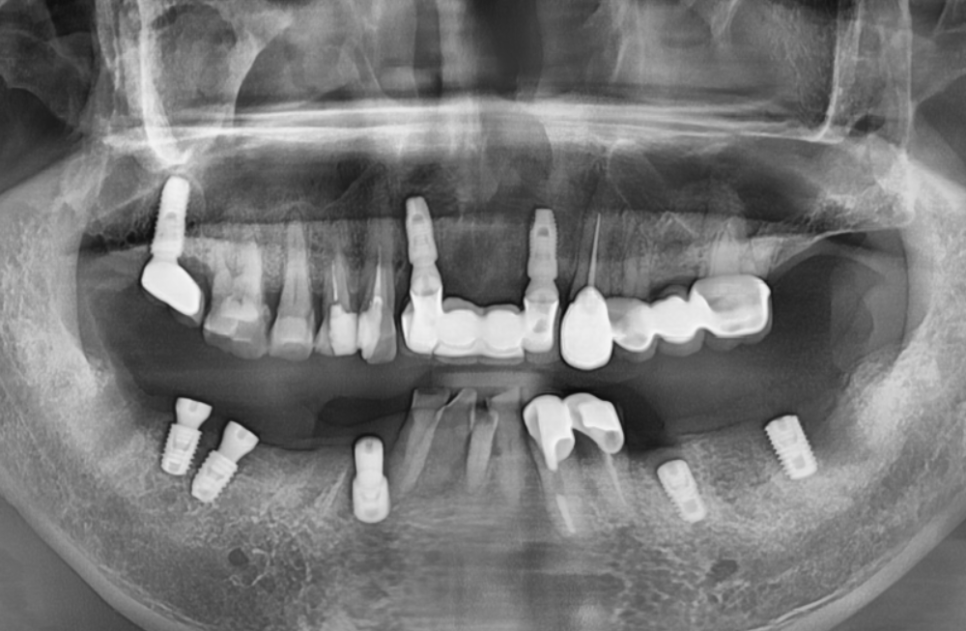

3개월의 기다림 끝에,

양쪽 어금니 모두

임플란트 보철이 완성되었습니다.

250905

흔들리고 냄새나던 브릿지 대신,

단단하게 고정된 임플란트가 생기니

무엇보다 '씹는 맛'이 다르다고 하십니다.

250403 (전) 250905 (후)